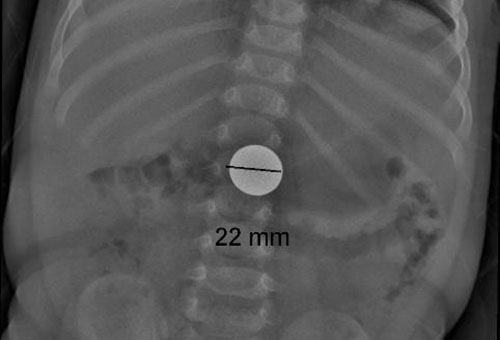

rebenok proglotil monetki nominalom 5 i 10 somov popal v bolnicu